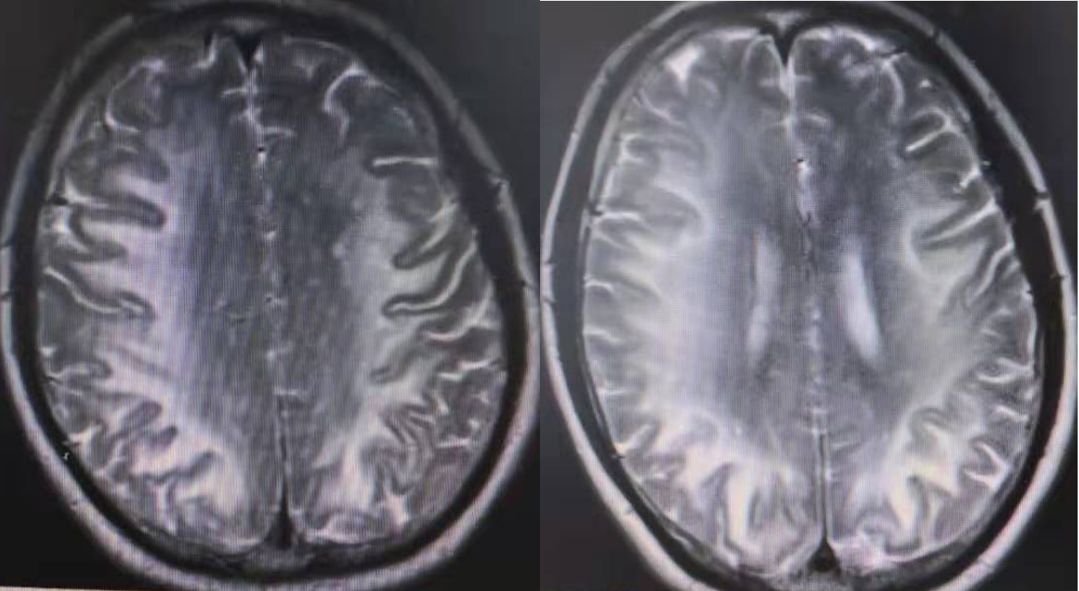

头颅MRI:可见右侧颞枕交界皮质下白质、额顶交界区半卵圆中心两处病灶,呈圆形卵圆形,T2高信号,环形弥散受限,对应区域ADC反转不明显。

诊断: 同心圆硬化(Baló’s concentric sclerosis)

临床表现:该病临床表现并不特异,可以模拟卒中急性起病,也可以表现为典型脱髓鞘疾病一样的渐进发展。其诊断最关键依靠MRI表现。

MRI表现:Baló’s 在T1像的特点是多个等、低信号交替的同心圆,在T2加权序列上表现为围绕高信号圆心(风暴眼)的高低信号环,也有其他模式如玫瑰、康乃馨甚至马赛克形状的报道。

病灶有轻微水肿。DWI序列可见弥散受限,多位于病灶边缘。增强序列可见强化,多位于病灶外周边缘,也可见到与T2高信号匹配的多层环形强化。